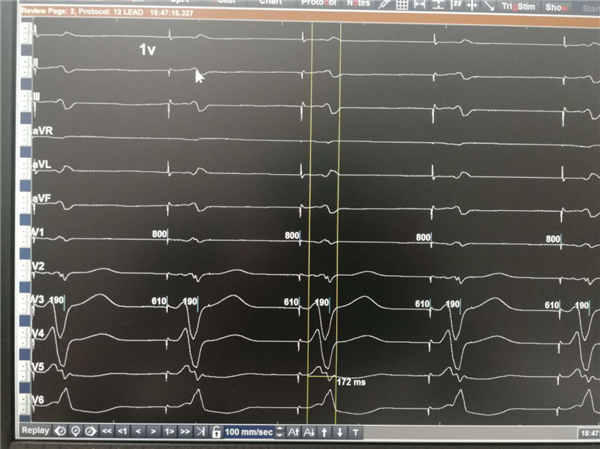

团队术前缜密讨论,充分考虑多个结局,多种策略。手术由郑强荪主任,韩振华副主任,薛嘉虹副教授,王新宏副教授及导管室护士王军、杨宏斌共同完成。团队先为患者行左心室电极植入冠状静脉窦的经典CRTD,但患者冠状静脉窦分支条件较差,左侧后支迂曲盘旋,给操作带来极大的困难,经多次尝试左室电极仍不能植入成功,郑强荪主任、韩振华副主任带领的团队迅速改变策略,与时俱进,决定行左束支区域起搏。另外患者在拔除原右室电极时又因电极与上腔静脉入口处粘连拔除困难,再次为手术带来障碍,最终经团队6小时的不懈努力,手术顺利完成。术后心电图QRS波群由原来的210ms缩窄为160ms,患者心功能明显改善。

术中左束支起搏